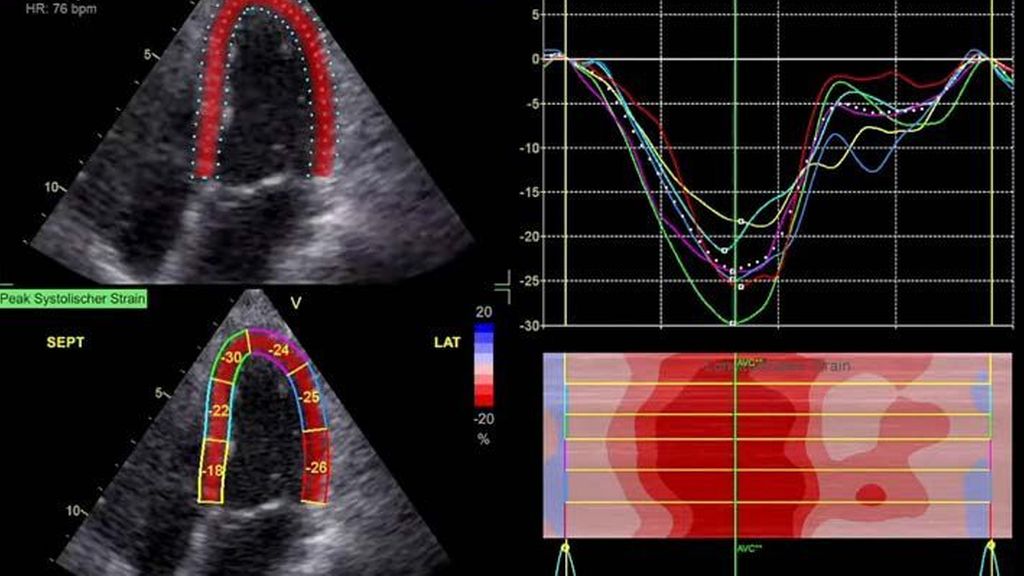

Die moderne Echokardiografie bietet die Möglichkeit einer hämodynamischen Evaluation in Ruhe wie auch bei „point-of-care“-Belastung. „Strain imaging“ und „myocardial work“ können neben bekannten Parametern, wie der Ejektionsfraktion (EF) und der Myokardmasse, ergänzend zur Diagnostik von Herzerkrankungen beitragen.

Moderne Messparameter wie „strain imaging“ geben diagnostische und prognostische Information.

Im Echolabor des Pyhrn-Eisenwurzen Klinikums Steyr wird jede Form der Myokardwandverdickung mittels einer vollständigen Standardechokardiografie untersucht.2 Dabei wird auch ein Fokus auf die kontrastmittelunterstützte Sonografie gelegt, um die tatsächliche Dicke des Myokards zu vermessen.3 Die Verdickung sollte optimalerweise mittels 3D-LV-Massenmessung erfolgen. Die Messung im 2D-Bild ist dahingehend unterlegen. Ebenso wird jede Myokardwandverdickung mittels 2D-„strain imaging“ in der transthorakalen Echokardiografie (TTE) untersucht.4–6 Der „strain“ ist eine Messung der longitudinalen Funktion des Herzens (Video 1).

Der erste Fall beschäftigt sich mit einem Patienten mit einer hypertrophen Kardiomyopathie (HCMP). Er gibt eine deutliche Belastungsdyspnoe sowie einen ausgeprägten Leistungsknick an. Es wurde infolgedessen eine Untersuchung mittels standardisierter Echokardiografie inklusive „strain imaging“ durchgeführt. Der globale longitudinale „strain“ (GLS) mit –16% in Ruhe war gering reduziert. Es konnte kein relevanter LVOT-Gradient in Ruhe nachgewiesen werden. In der Belastungssituation (Handgrip, Valsalva, Kniebeugen und als Vorbereitung zur Untersuchung ein ausgiebiges Frühstück und Kaffee sowie ein am Vorabend konsumiertes Bier) konnte bei Kniebeugen mit einer Herzfrequenz von 126/min ein Spitzengradient bis 52mmHg dargestellt werden. Somit ergibt sich die Diagnose einer HOCMP mit einem belastungsinduzierten Gradienten. Bei bereits bestehender und ausgereizter Therapie unter Betablocker besteht die Indikation zur Therapie mittels des kardialen Myosininhibitors Mavacamten (Klasse-IIa-Empfehlung laut ESC).1 Darunter verbesserte sich die klinische Situation des Patienten deutlich, der Patient konnte uneingeschränkt Sport ausüben. Über die Zeit kam es zu einer geringen Reduktion der LV-Masse und einer geringen Zunahme des LV-„strain“. Die Belastungssituation zeigte durchwegs normale „strain“-Werte mit –20% (mit regionaler Reduktion bei Myokardwandverdickung im Sinne einer Hypertrophie). Die myokardiale Arbeit beim konkreten Patientenfall ist ebenso in Ruhe im grenzwertigen und unter Belastung im guten Normalbereich.6,8,9 Der Patient ist derzeit unter 5mg Mavacamten einmal täglich optimal eingestellt. Die EF in Ruhe ist konstant bei 50–55%. In Video 2 werden unterschiedliche Gradienten dargestellt, um eine HOCMP mit LVOTO von z.B. einer Mitralklappeninsuffizienz zu unterscheiden.Die Verdachtsdiagnose wurde mithilfe der Echokardiografie gestellt und durch das septal betonte „patchy“ LGE im MRT bestätigt.1,5

Andere Formen der Myokardwandverdickung, die mit „strain“ und MRT gut dargestellt werden können, sind einerseits die Differenzierung der Auswirkung der arteriellen Hypertonie (weiblich, 72a) bei Vorliegen einer Herzinsuffizienz mit normaler EF, einem GLS von –15,4%, einem LA-„strain“, in Reservoirphase 25% bei gering verlängerten T1-Zeiten im MRT. Andererseits kann Steroidabusus (männlich, 44a) zu einem reduzierten „strain“ mit gering verlängerten T1-Zeiten und einer Normalisierung der bildgebenden Befunde nach 2 Jahren nach Absetzen führen bzw. eine Mitochondriopathie (männlich, 32a) zu einer unklaren Myokardverdickung mit diffus reduziertem „strain“ und reduzierter LV-Funktion.4,11,12